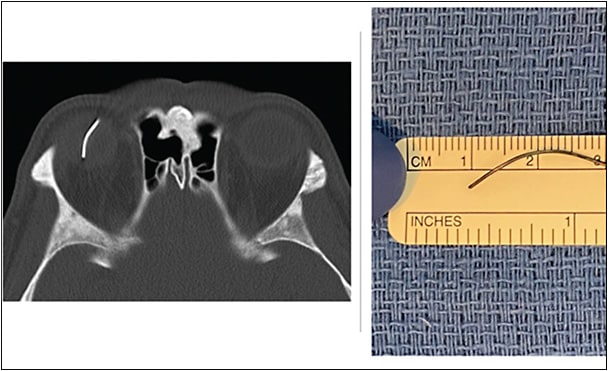

Diagnosing retained IOFBs can be challenging, especially if they are small and nonmetallic. Ocular imaging using CT scan (axial 1-mm cuts with sagittal and coronal reconstruction images) should be performed in all suspicious cases (Figures 2 and 3). Identification of the IOFB depends on the radiodensity of the material.44 Helical CT scanners have a resolution of 0.6 mm,45,46 but small plastic, glass, or wood pieces (<0.5 mm) can be missed, especially if there is extensive VH and the globe is disorganized due to injury (Figure 4). Such cases may require further investigation using MRI,47,48 provided that the IOFB is not magnetic. Newer ocular ultrasonography machines are very sensitive and may detect extremely small radiolucent materials. Use of echography in the setting of an open-globe injury requires an experienced echographer, because undue pressure on the globe can exacerbate the extent of injury and increase the risk of infection.